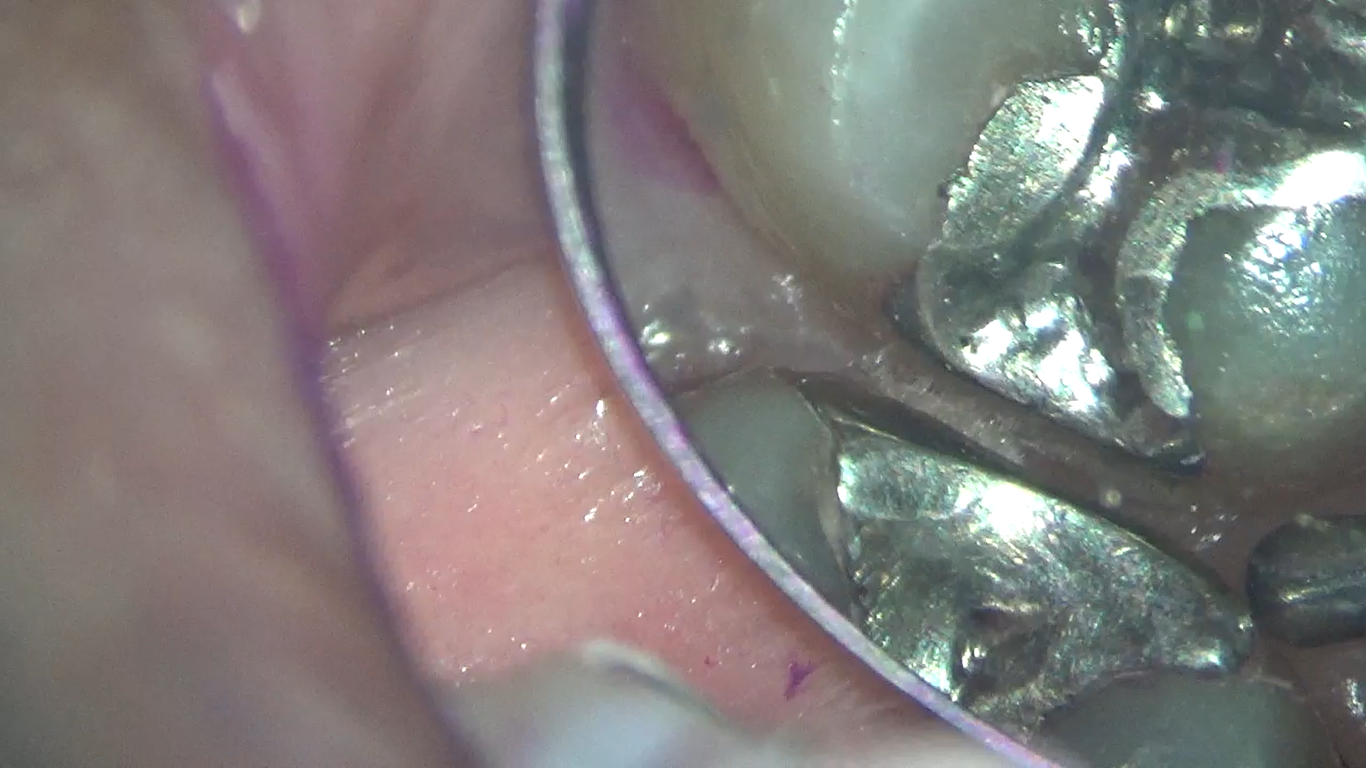

こんにちは!南館歯科クリニックの歯科衛生士 山崎です。 今回は、歯石について少し具体的にご説明します。 画像説明 歯周専門治療中に歯石除去をするところです。 黒く色づいている歯石が両サイドの歯にく…